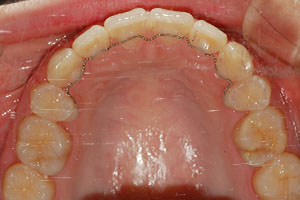

치료증례 전후사진

Before & After